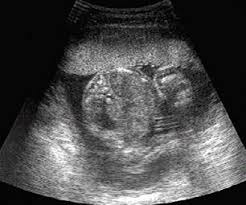

Twenty weeks into their third pregnancy, Rachel and Silvano Pifori got more excitement than they hoped for. After reviewing two ultrasounds, their doctor delivered devastating news.

“He looked at us and said things look very grim. And he began going through a laundry list of things that were wrong with the baby,” Rachel said, “very little amniotic fluid around, problems with the brain, problems with the heart, there’s no bladder, no kidneys, skin edema, just went on and on and on. I remember feeling very out of control and very helpless and certainly very sad; and also trying to figure out how am I going to explain this to the kids - how are they going to understand this?”

The ultrasounds also revealed that Rachel had full placenta previa, a condition where the placenta attaches to the cervix underneath the baby. If Rachel went into labor she could bleed to death.

As Rachel neared her due date, she had one more ultrasound to check the condition of the placenta previa. She asked the technician to check the baby as well. They were stunned when he told them what he saw.

“’There’s the baby’s bladder.’ And I said, ‘But the baby doesn’t have a bladder,’” Rachel said. “And he said, ‘Sure it does and it’s full of urine.’ I said, ‘Excuse me?’ I said, ‘The baby doesn’t have any kidneys.’ And he said, ‘You don’t have any urine in the bladder without any kidneys.’”

The technician called in the doctor and together they looked over the findings. Even the placenta previa had been corrected.

“It was so fascinating to watch the doctors confused,” Rachel said. “I remember thinking, ‘This is God, because they don’t know what’s going on here.’ The doctor looked at us and he said, ‘Don’t quote me on this, but I don’t see any of the problems that they say exist.’”